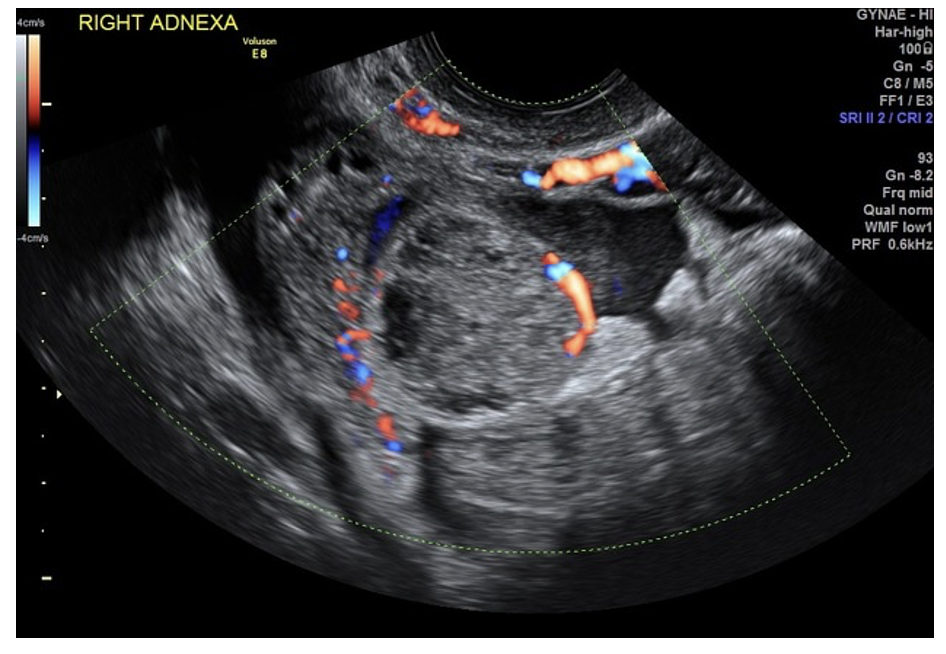

Suggestive signs: heterogenous adnexal mass, “ring of fire” on Doppler, pseudogestational sac, tubal ring sign

Budorick N, Ovarian ectopic pregnancy. Case study, Radiopaedia.org (Accessed on 19 Nov 2025) https://doi.org/10.53347/rID-208112

Knipe H, Tubal ectopic pregnancy. Case study, Radiopaedia.org (Accessed on 19 Nov 2025) https://doi.org/10.53347/rID-36812.